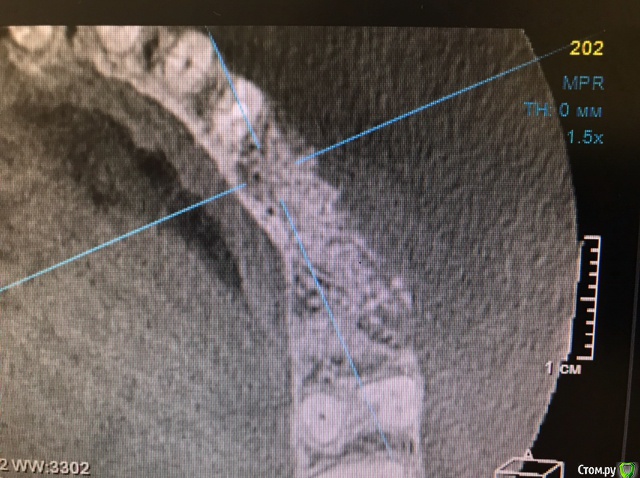

колесников Опубликовано 15 марта, 2019 Автор Поделиться Опубликовано 15 марта, 2019 Вот так выглядит интегрированый графт и соответственно не созревший. Время ожидания примерно равнозначное Ссылка на комментарий

колесников Опубликовано 16 марта, 2019 Автор Поделиться Опубликовано 16 марта, 2019 (изменено) Ну как бы тут все очевидно. Слева стала костью,справа нет. Но должен вам отметить,что даже в случае неудачи (как кажется)потери нет. Задача стояла не увеличить объём для имплантации или укрыть Имплант,а снять напряжение с вершины гребня и дать созреть десне. Имплант в нативной кости,он интегрирован,десна успела созреть за это время,возможно будет не так объёмно как хотелось бы,но у меня в запасе этап раскрытия ,фдм зарос ,есть с чем поработать. Все что не интегрировалось ,лизируется самостоятельно,выскребать ничего не нужно,ещё подождать. Изменено 16 марта, 2019 пользователем колесников Ссылка на комментарий